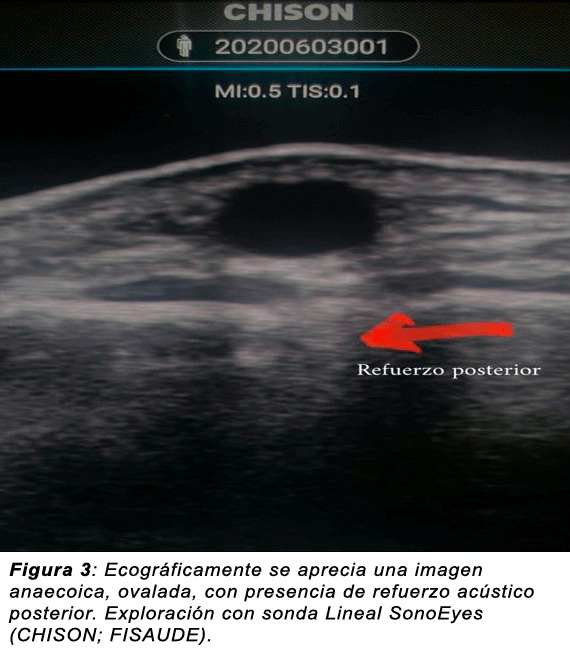

Refuerzo acústico posterior: Cuando se produce una amplificación de los ecos de zonas posteriores a una colección líquida, lo cual trae como consecuencia un aumento de la ecogenecidad que se observa detrás de las colecciones liquidas. Ejemplo: quistes sinoviales o gangliones.